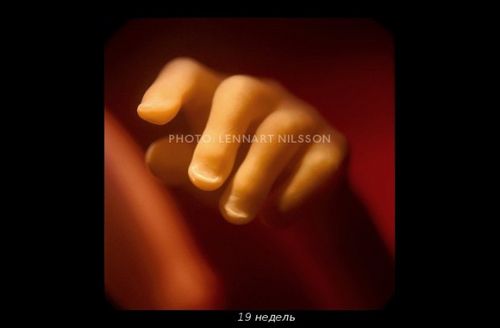

Відкрити завісу таємниці зміг шведський фотограф Леннарт Нільсон. Протягом 10 років він знімав, як розвивається ембріон від моменту зачаття і до народження. Подивитися його роботи ви можете нижче.

У 1965-му році Нільсон видав фотокнигу «A Child is Born», яка до сих пір залишається однією з найбільш продаваних.

Можна добре розглянути личко малюка. Як думаєте, він схожий на тата? Дитина активно моргає, відкриває ротик і удосконалює хапальний рефлекс.